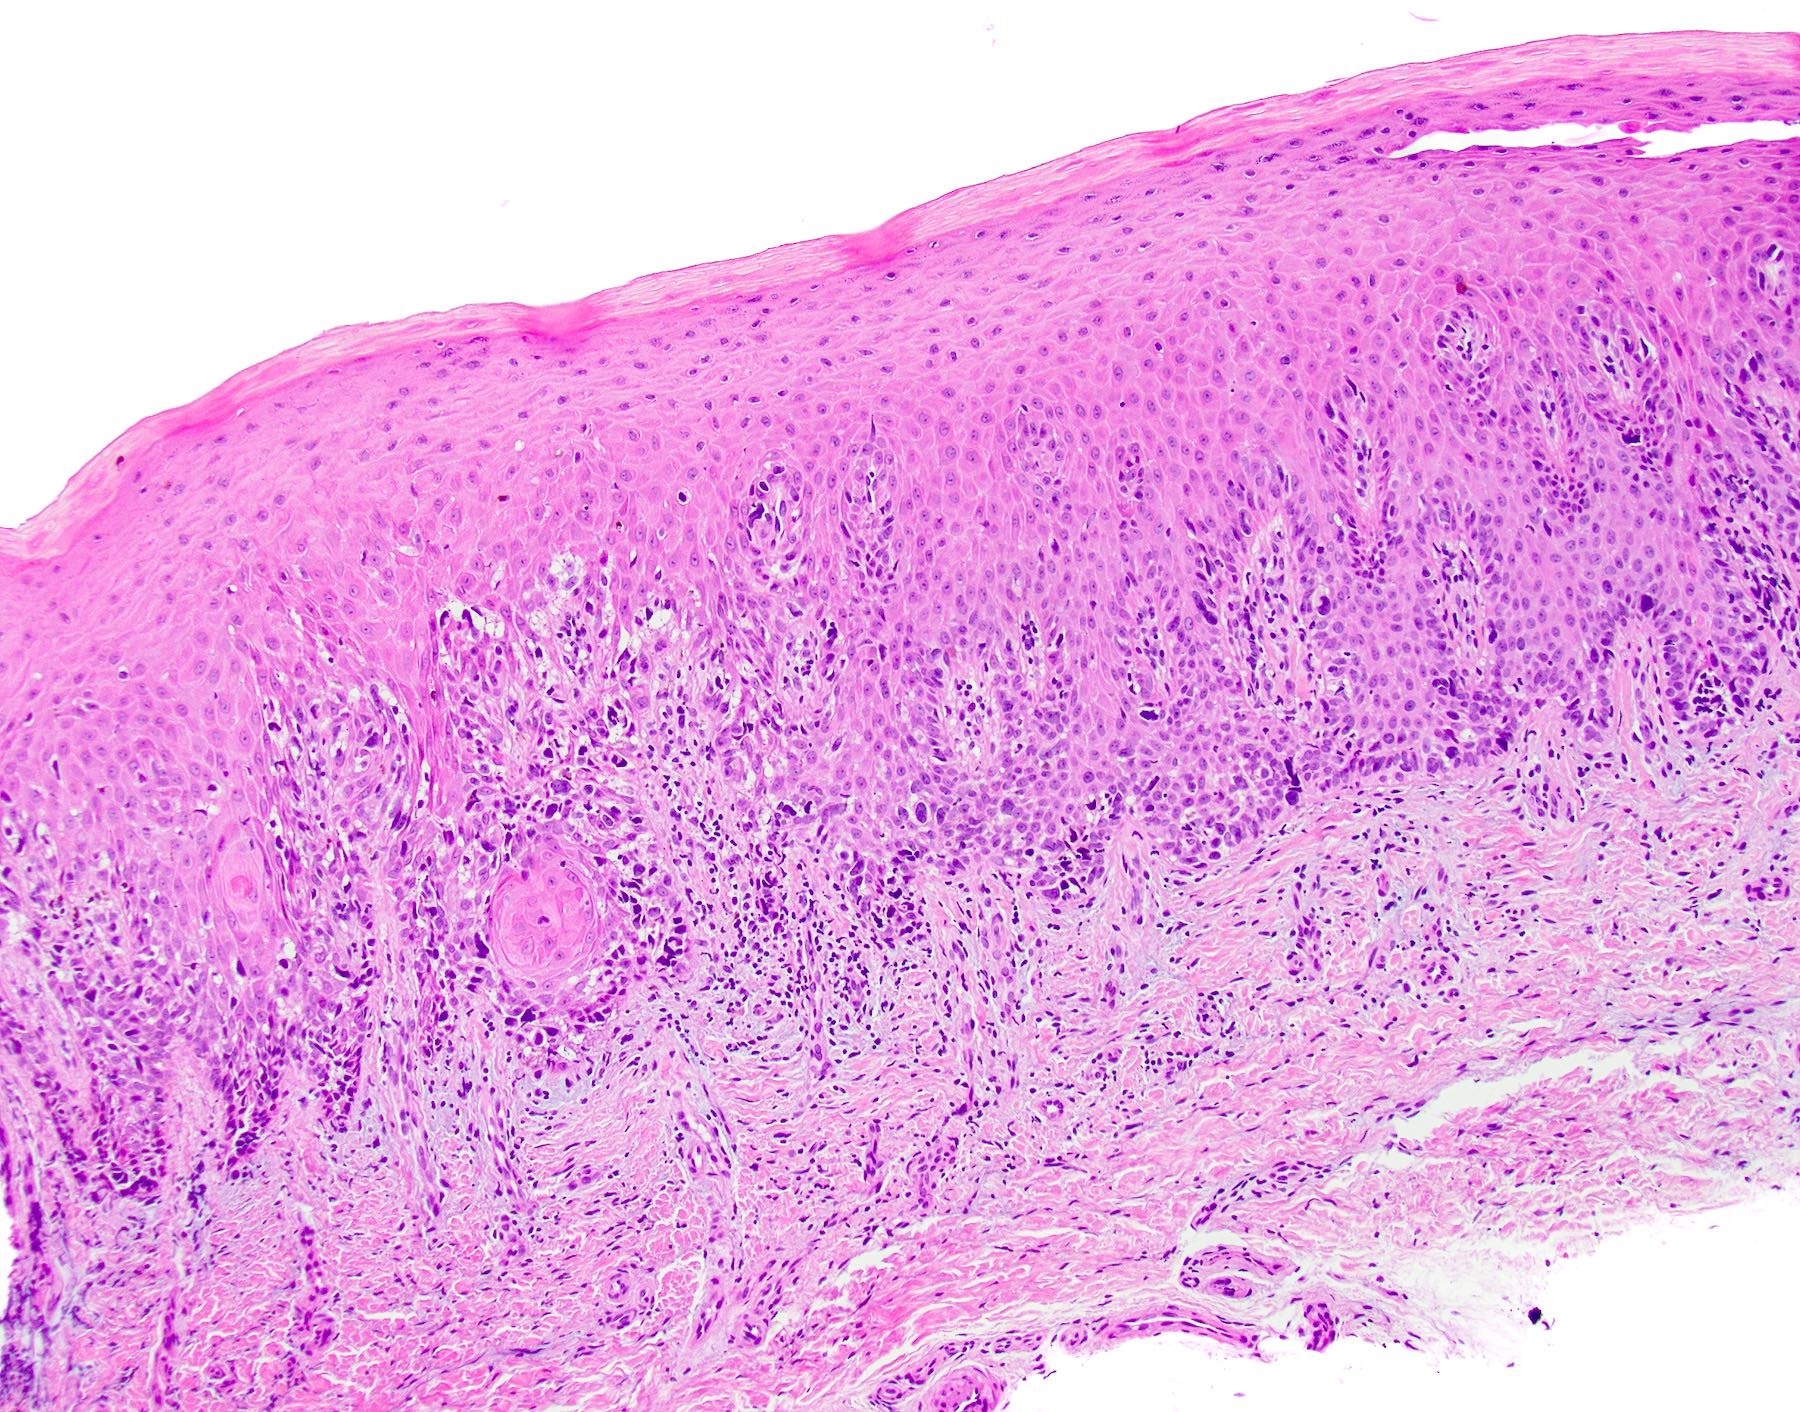

• Thick elongation of the overlying epithelium with bulbous or sometimes jagged / sharp, interconnecting rete ridges (Am J Dermatopathol 2011;33:112)

• May exhibit keratin pearl formation: concentric layers of keratinocytes with central keratinization (Am J Dermatopathol 2011;33:112)

• Lacks significant nuclear atypia; although mitotic figures may be seen, they are not numerous or atypical (Am J Dermatopathol 2011;33:112)

• Replacement of underlying fibrous stroma with sheets of pale, basophilic, plump granular cells suggests that the overlying epithelial proliferation is likely associated with granular cell tumor

PEH in granular cell tumor PEH in granular cell tumor

PEH in granular cell tumor

Practice question #2

A patient presents with a yellow nodule on the tongue. What is the diagnosis?

1. Frictional keratosis

2. Granular cell tumor with overlying pseudoepitheliomatous hyperplasia

3. Squamous cell carcinoma

4. Verrucous carcinoma

Practice answer #2

B. Granular cell tumor with overlying pseudoepitheliomatous hyperplasia (PEH). Microscopic sections show a dome shaped mass of pale, basophilic, plump granular cells surfaced by hyperkeratotic and hyperplastic epithelium. Although the rete ridges are significantly proliferative and demonstrate keratin pearls, overt cytologic atypia is not appreciated. This proliferative pattern of the epithelium is termed pseudoepitheliomatous hyperplasia and is known to be associated with granular cell tumors. Answer A is incorrect because although there is a thickened layer of parakeratin, this answer choice ignores the replacement of the fibrous stroma by plump granular cells. Answer C, a common pitfall in the diagnosis of this tumor, is incorrect because although the epithelium is proliferative, prominent cytologic atypia is not appreciated. The pathologist must be keen in recognizing the underlying replacement of the fibrous stroma with plump granular cells and must know that granular cell tumors characteristically show PEH in many cases. Answer D is incorrect because verrucous carcinoma would show keratin clefting and prominent, bulbous, plunging rete ridges that push into the underlying muscle.